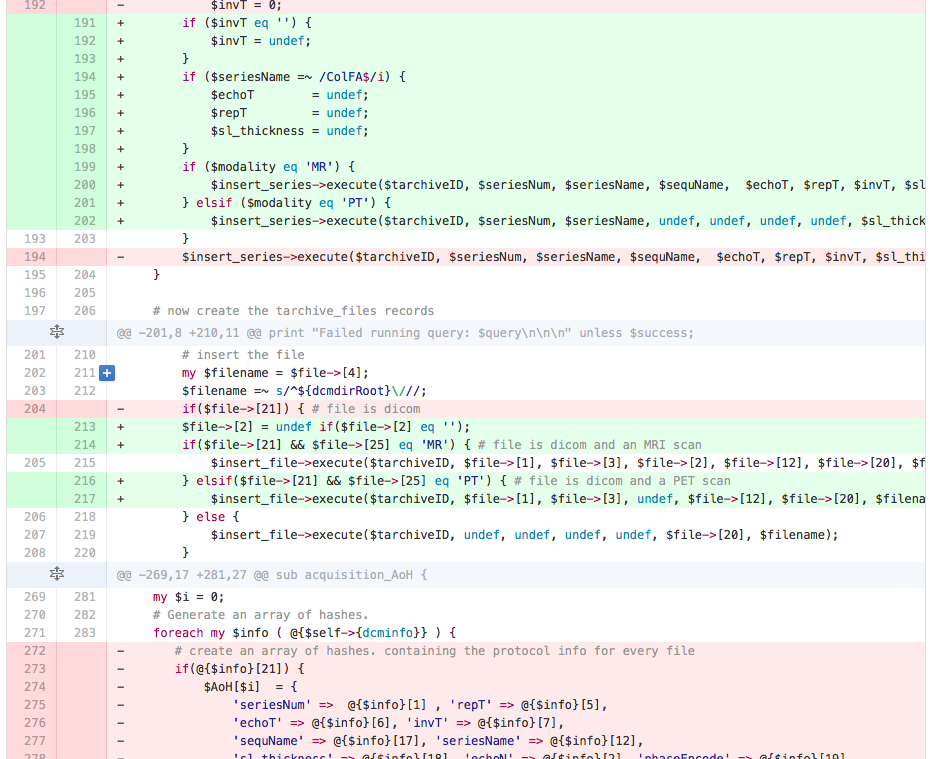

Automated PET recognition

Automated PET recognition

Enhanced DICOM anonymization

- Going dcmtk free -- PYDICOM

- CONDA

- Satra knows everything!!

Enhanced DICOM anonymization